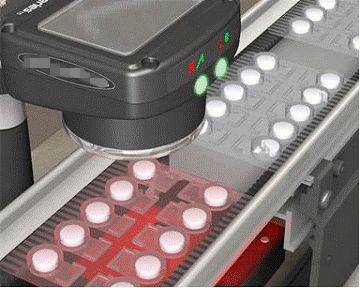

19.药品的缺陷检测

通过机器视觉可以检测药片在包装时可能产生的药片缺损、蚊虫污染、漏装、胶囊漏粉等不良情况进行检测